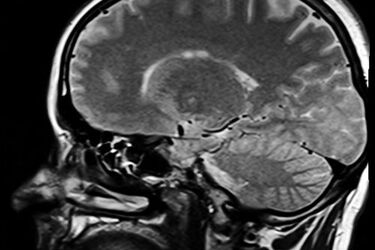

Kolejki na badania rezonansem magnetycznym są bardzo długie. Najbliższe wolne terminy sięgają grudnia 2015 roku. Poza Białymstokiem czeka się jeszcze dłużej. Podlascy pacjenci będą mogli teraz łatwiej dostać się na badania rezonansem magnetycznym. Narodowy Fundusz Zdrowia podpisał kontrakt z Niepublicznym Zakładem Opieki Zdrowotnej przy ul. Marjańskiego 3 w Białymstoku. Badania będą wykonywane w ramach ubezpieczenia. W NZOZ Kendron można wykonać m.in.: rezonans głowy, stawów, jamy brzusznej oraz mózgu.